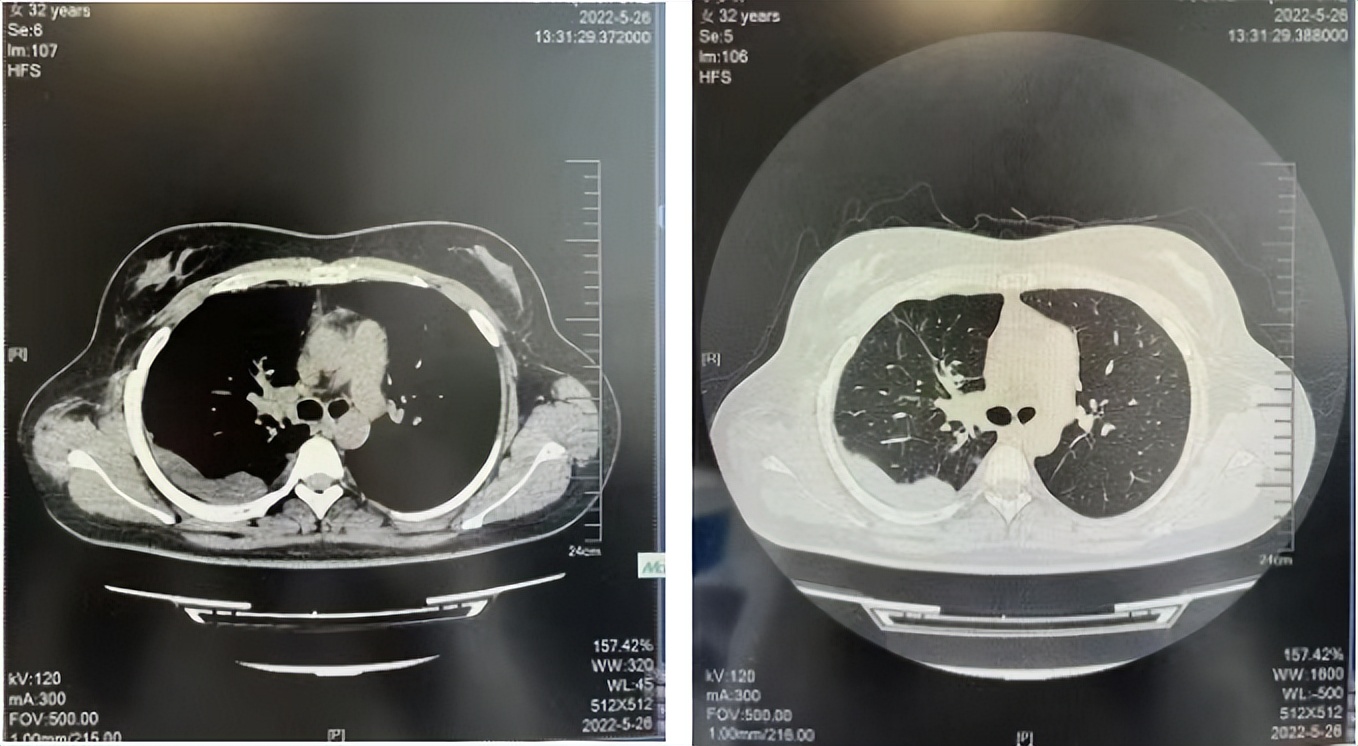

2016年1月复查CT提示支气管截断可见新发小结节,一线治疗采用培美曲塞+DDP方案化疗4周期(培美曲塞3.36,DDP 480mg)。化疗后复查胸部CT:右肺见不规则结节样影,最大层面大小约19mm*8mm,较前比较明显增大,疗效评估PD。2017.3-2017.4予单药多西他赛化疗3周期,疗效评估SD。2018年5月末复查CT提示结节较前增大,评效为PD,2018年6-10月予多西他赛+CBP化疗4周期,疗效评估SD。2022年5月患者出现活动后气短,复查胸部CT示右肺膨胀不良;右侧胸腔积液增多。胸腔积液包埋病理示符合肺腺癌细胞。行NGS基因检测:EML4:exon13-ALK:exon20融合。PD-L1(克隆号22C3)TPS<1%。

临床诊断:右肺上叶恶性肿瘤rT0N0M1a IVA期(第9版分期);恶性胸腔积液。

诊疗经过:2022年5月始口服克唑替尼3个月,出现肝功能异常(DILI 2级伴临床症状),改用恩沙替尼靶向治疗至今,目前评效为维持PR。恩沙替尼应用期间出现轻度肝功能异常(DILI 1级),对症处理后好转。截止目前PFS 33个月。

2022.05

2022.08